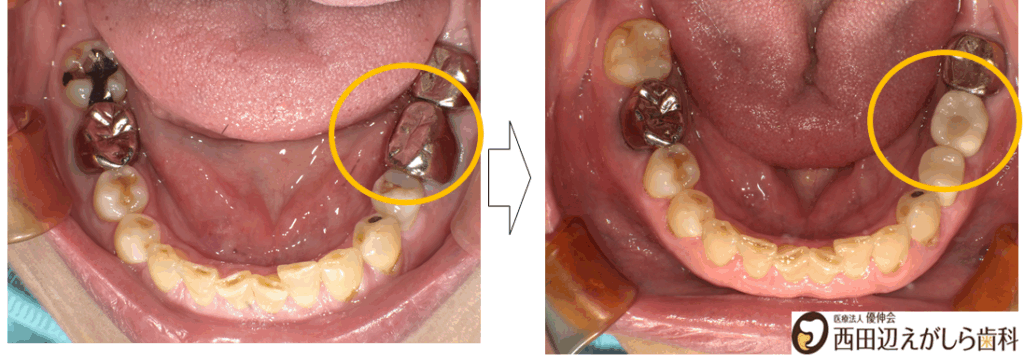

初診時にレントゲン検査を行ったところ、左下6番の歯の根の先に感染が広がっており、根尖病巣が認められました。これが、繰り返す腫れや、噛んだときの痛みの原因になっていると考えられました。

さらに詳しく確認すると、病巣は比較的大きく、歯根も短くなっており、歯にヒビが入っている可能性も否定できない状態でした。そのため、保存は難しいと判断し、抜歯が必要であることをご説明しました。

インプラント埋入後は、約3か月の治癒期間を設け、インプラントが骨としっかり結合していることを確認しました。その後、口腔内スキャナーを用いて上部構造製作のためのスキャニングを行い、最終的な被せ物を装着しました。